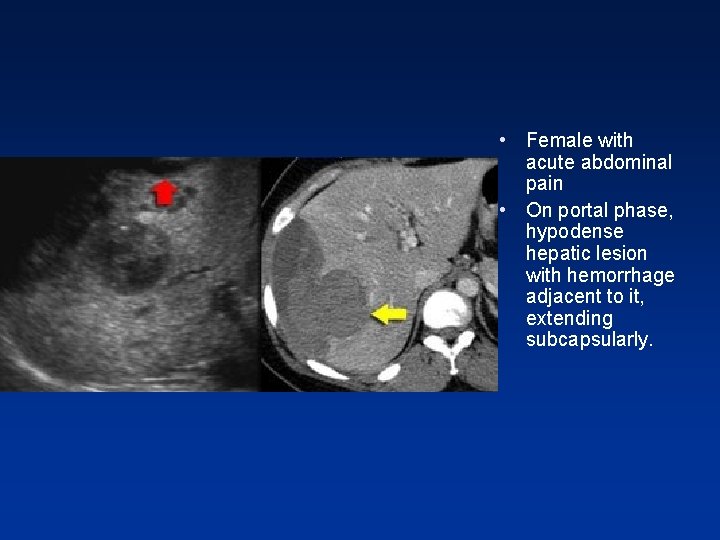

• Best diagnostic clue: spherical well defined hypervascular and heterogenous mass due to fat & hemorrhage. • Symptomatic in 80%-abdominal pain- ( FNH asymptomatic in 80%) • 98% in yoyung females taking oral contraceptives • Not seen in males unless on anabolic steroids or with glycogen storage disease.

• Adenoma showing capsule in delayed phase

• Female with acute abdominal pain • On portal phase, hypodense hepatic lesion with hemorrhage adjacent to it, extending subcapsularly.

• Fat in adenom a

• Hemorrhage in adenoma